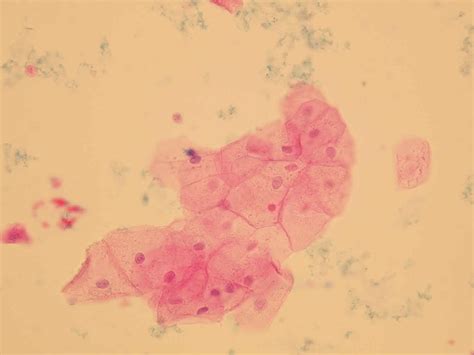

Urine Epithelial Squamous Cells

Urine analysis is a common diagnostic tool used in medical settings to assess various aspects of a patient's health. Among the many components examined in a urine sample, urine epithelial squamous cells play a crucial role in diagnosing certain conditions. These cells, which originate from the squamous epithelium lining the urinary tract, can provide valuable insights into the health of the urinary system. Understanding the significance of urine epithelial squamous cells and their implications in diagnostic processes is essential for healthcare professionals and patients alike.

Urine epithelial squamous cells are flat, scale-like cells that line the distal urethra and the external genitalia. These cells are typically found in small numbers in a normal urine sample. However, an increased presence of these cells can indicate various conditions, including infections, inflammation, or even more serious issues like cancer. The presence of urine epithelial squamous cells in urine samples is often noted during a routine urinalysis, which is a standard test performed to evaluate the overall health of the urinary system.

During a urinalysis, a healthcare provider will examine the urine sample under a microscope to identify and count the number of urine epithelial squamous cells present. The results are typically reported as the number of cells per high-power field (HPF). A normal urine sample may contain a few squamous cells, but an elevated count can indicate a potential issue. The interpretation of these results is crucial for accurate diagnosis and treatment.

Here is a general guide to interpreting the presence of urine epithelial squamous cells:

Number of Squamous Cells per HPF Interpretation

0-5 Normal

6-10 Mildly elevated

11-20 Moderately elevated

21+ Significantly elevated